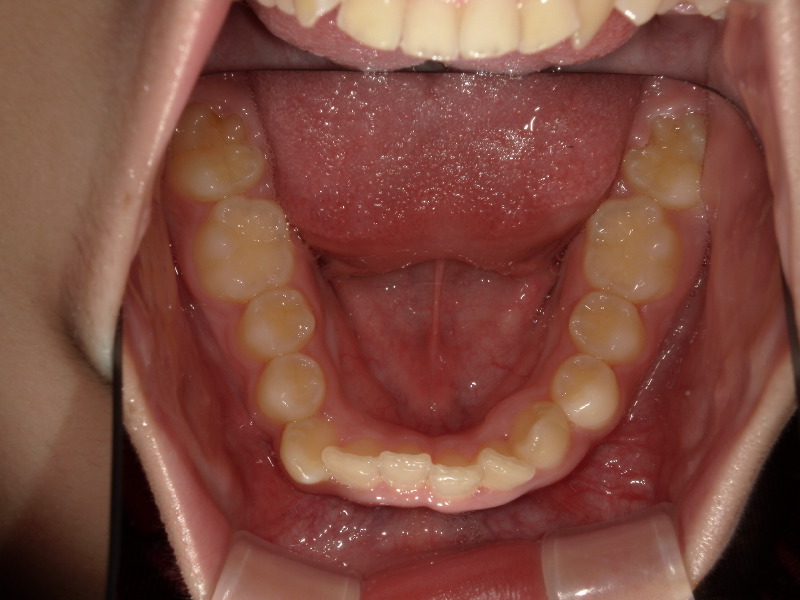

検査時の状態

上下の噛み合わせが深く、強く噛み込んでいるため下の歯が見えていません。

また下の歯並びもがたつきがあります。

この時既に全て永久歯です。

下の歯並び

こちらも一年半の経過です。

既に永久歯列なことと、一番奥の親知らずの手前まで歯が出てきていますが、綺麗に入ってきています。